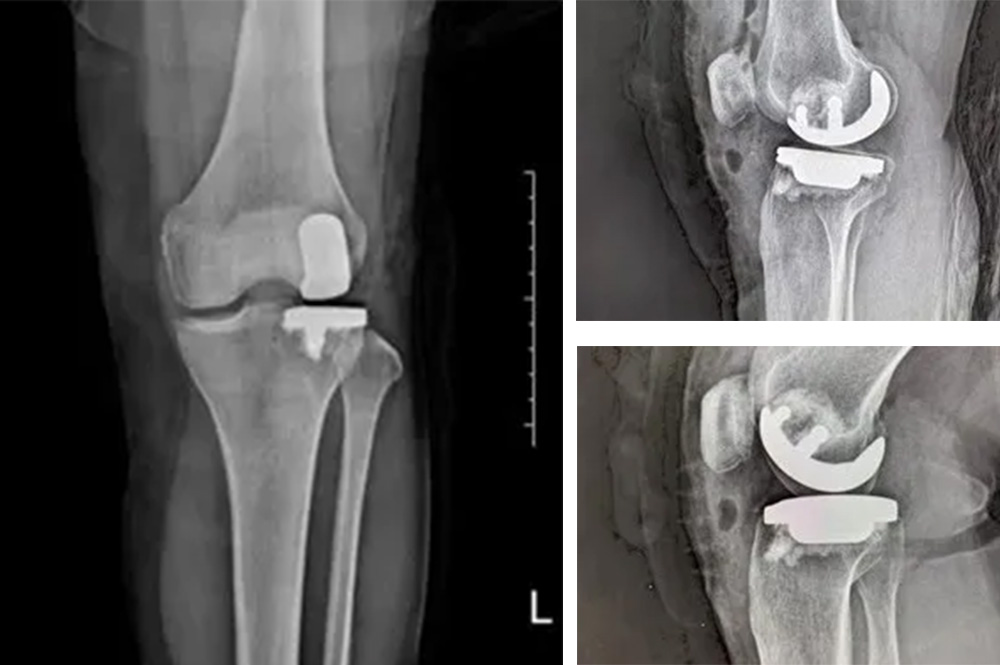

經(jīng)過詳細(xì)的體格檢查、影像學(xué)評估和三維重建,醫(yī)療團(tuán)隊確認(rèn)鮑奶奶的情況非常適合進(jìn)行膝外側(cè)單髁置換術(shù)。這種微創(chuàng)手術(shù)創(chuàng)傷小、恢復(fù)快,能夠最大程度保留膝關(guān)節(jié)的自然結(jié)構(gòu)和功能。

手術(shù)當(dāng)天,骨科團(tuán)隊采用微創(chuàng)切口,僅約8厘米,遠(yuǎn)小于傳統(tǒng)全膝關(guān)節(jié)置換手術(shù)切口。術(shù)中精準(zhǔn)定位,僅置換病變的膝關(guān)節(jié)外側(cè)間室。

手術(shù)使用了最新的單髁假體系統(tǒng),這種假體設(shè)計更符合人體工程學(xué),能夠更好地恢復(fù)膝關(guān)節(jié)的自然運動軌跡。